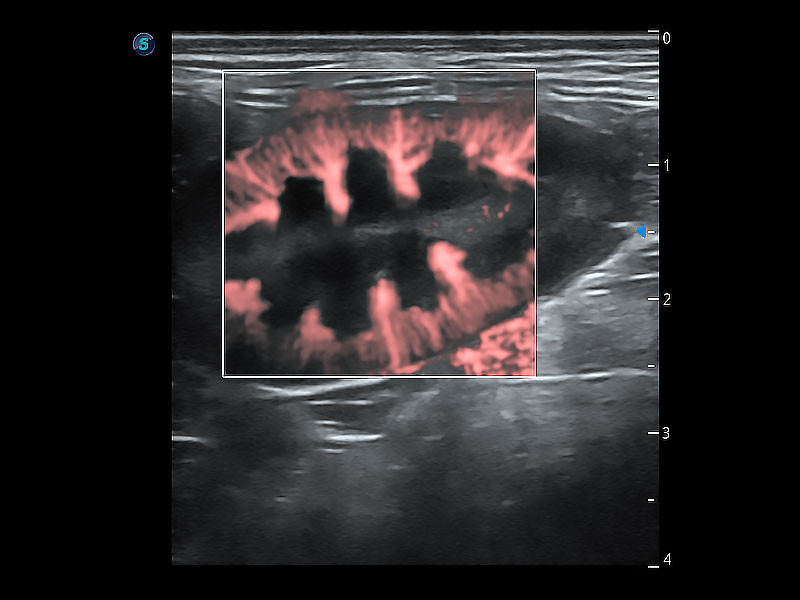

极大提升超低速微细血流的检出能力,同时更精准地滤除软组织和超声信号,为兽用医生提供以往无法通过常规血流获得的疾病诊断信息。

为精细结构及组织边缘提供高清晰度的图像和更大的成像视野。帮助减轻医生的用眼疲劳,快速精准获得测量的数据。